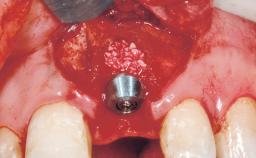

Immediate Flapless Placement of an Implant in a Maxillary Left Central Incisor Site

A 42-year-old female patient was referred to our clinic at the School of Dentistry of the University of São Paulo in November 2004, presenting a deficient restoration in the upper left central incisor. The clinical examination revealed no gingival retraction or any signs of gingival inflammation and, therefore, previous periodontal treatment was not considered. The patient presented a high lip line at full smile and a thin tissue biotype. This combination characterized a high-risk situation from an anatomic point of view, which required careful preoperative planning and cautious surgical execution.

Type of Implants One-Piece

Bone Augmentation No

Placement Protocol Immediate implant placement

Socket Integrity Sufficient, with intact bone walls

Bone Volume Sufficient, with intact walls